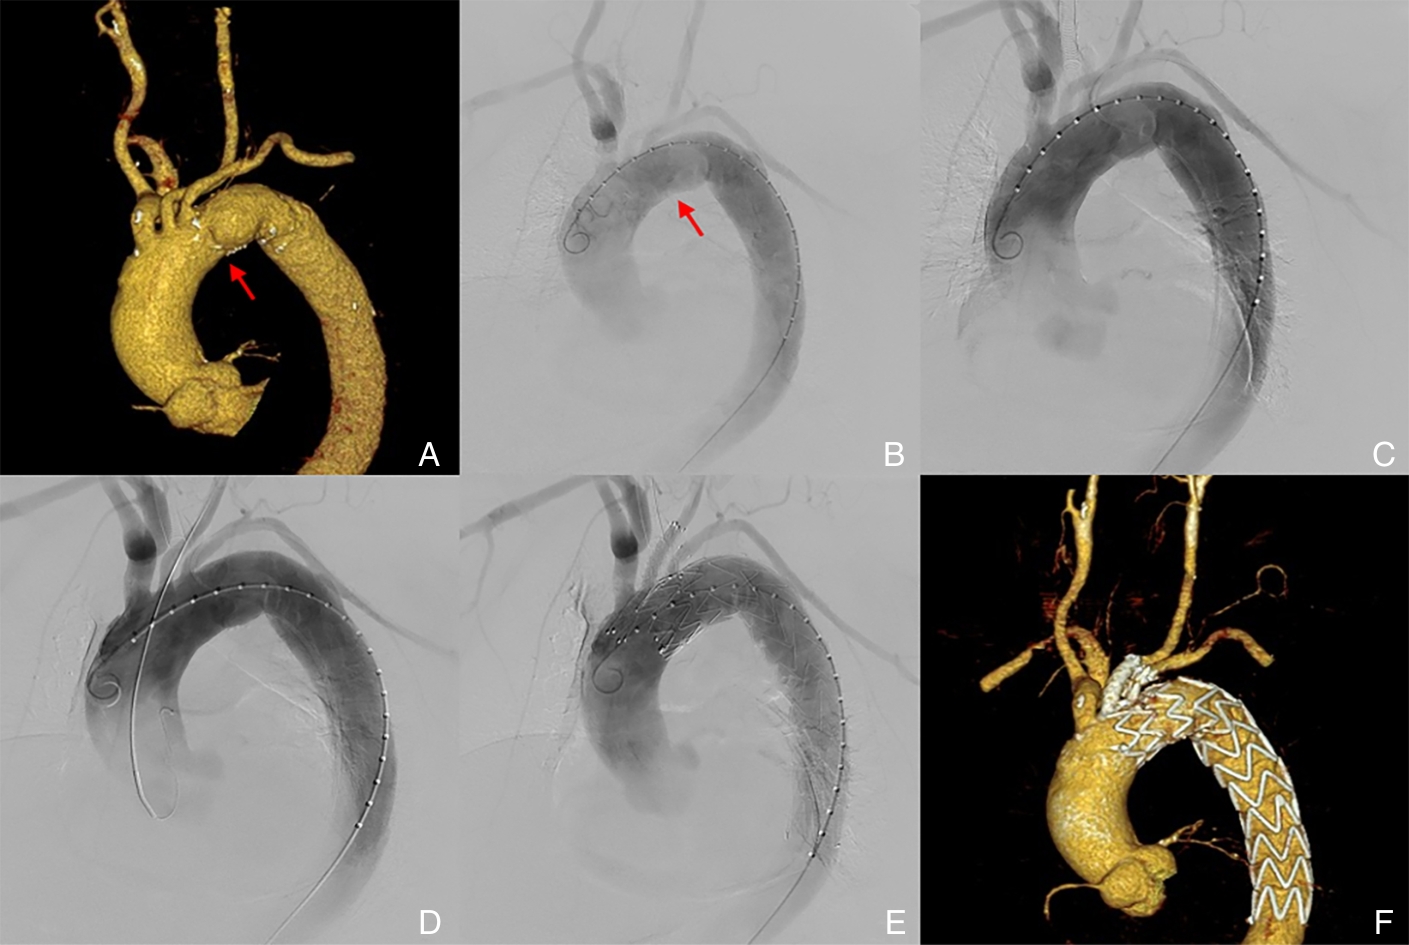

摘要:背景与目的 主动脉弓部疾病的腔内修复需兼顾病灶有效隔绝与弓上分支血管灌注,是当前血管外科领域的重要挑战。Castor分支型主动脉覆膜支架具备结构完整、一体化重建左锁骨下动脉(LSA)血流的优势,联合左颈总动脉(LCCA)烟囱支架技术,有望为近端锚定区不足的弓部病变提供微创、可行的治疗方案。本研究旨在评估该联合技术的初步可行性与安全性,为复杂主动脉弓病变的腔内治疗提供临床参考。方法 回顾性纳入2023年2月—2024年12月在中南大学湘雅二医院接受Castor分支型支架联合LCCA烟囱支架技术治疗的15例主动脉弓部疾病患者,分析其基线特征、手术过程、围手术期并发症及随访结果,评估技术成功率、并发症发生率及分支血管通畅率。结果 15例患者中男性11例,平均年龄63.8岁,病种包括主动脉夹层(33.4%)、弓部动脉瘤(53.3%)及穿透性主动脉溃疡(13.3%)。手术技术成功率100%,围手术期无死亡及严重并发症。随访时间4~26个月(平均12.9个月),期间无脑卒中、瘫痪、内漏、支架移位等并发症发生,LCCA与LSA通畅率均为100%。结论 Castor分支型主动脉覆膜支架联合LCCA烟囱支架技术在治疗近端锚定区不足的主动脉弓部病变中展现出良好的技术可行性与短期安全性,有望成为复杂主动脉弓腔内治疗的新选择。但仍需大样本、多中心、长期随访研究进一步验证其远期疗效与安全性。